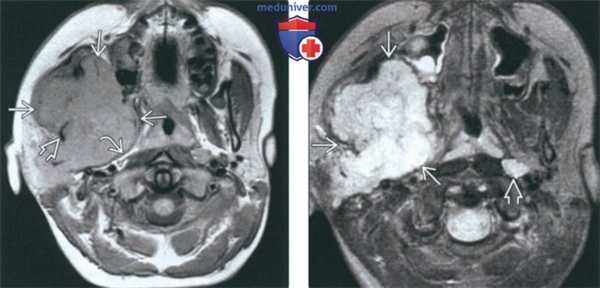

(Слева) МРТ Т1ВИ в аксиальной проекции. Саркома Юинга, локализующаяся в жевательном пространстве. Обратите внимание, что сигнал относительно здоровых мышц гиперинтенсивный. Нижняя челюсть разрушена, определяется лишь небольшой ее фрагмент. Жировая клетчатка окологлоточного пространства смещена в медиальную сторону.

(Справа) МРТ Т2ВИ FS, аксиальная проекция, тот же пациент. Неоднородный сигнал высокой интенсивности. Крупный лимфоузел в заглоточном пространстве слева представляет собой случайную находку.

(Слева) На аксиальной МРТ (Т1ВИ) в жевательном пространстве визуализируется саркома Юинга в виде огромного объемного образования с гиперинтенсивным относительно мышц сигналом. Ветвь нижней челюсти разрушена, на этом изображении виден лишь ее мелкий фрагмент. Полоска окологлоточного жира смещена кнутри.

(Справа) На аксиальной МРТ (Т2ВИ FS) у этого же пациента определяется неоднородный сигнал крайне высокой интенсивности в опухоли. Хорошо различимый заглоточный лимфоузел слева является случайной находкой.